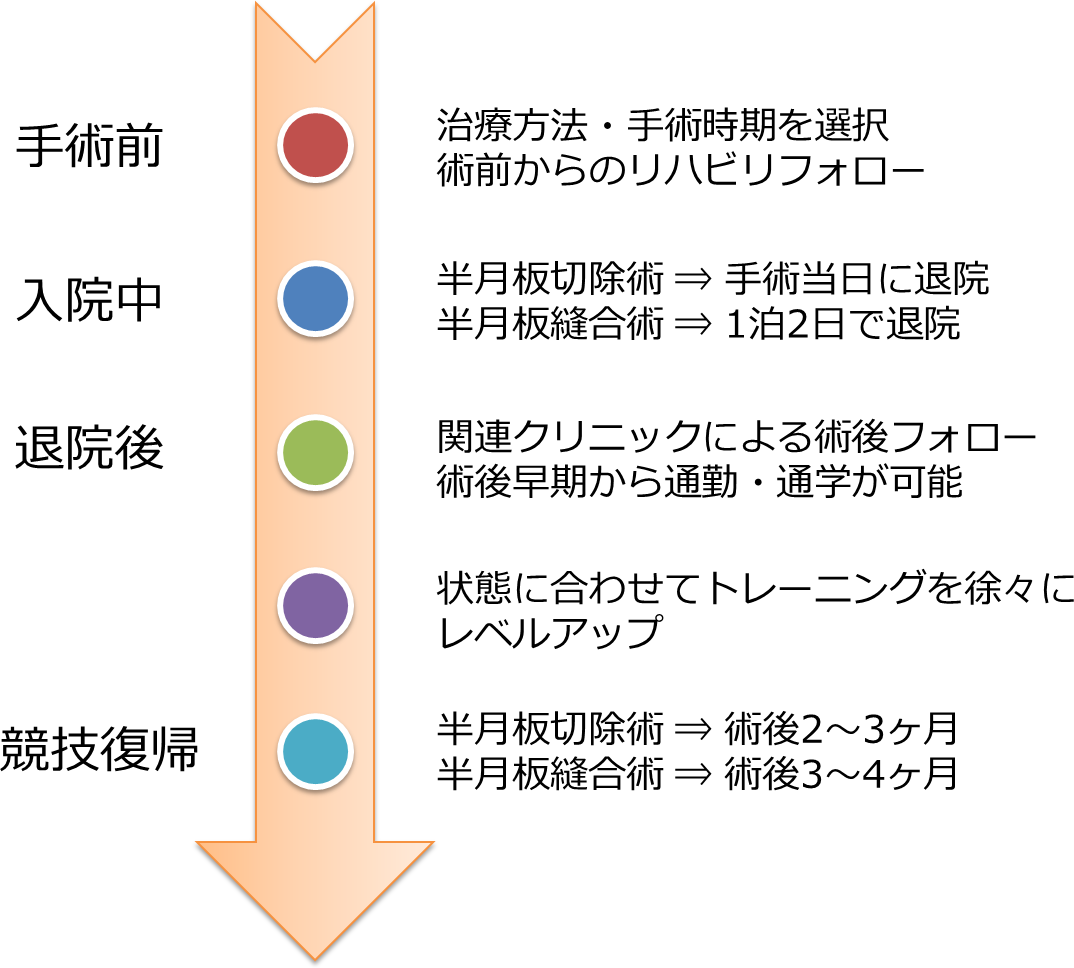

手術前から退院後までの流れは?

手術前からスポーツ復帰までの流れは?